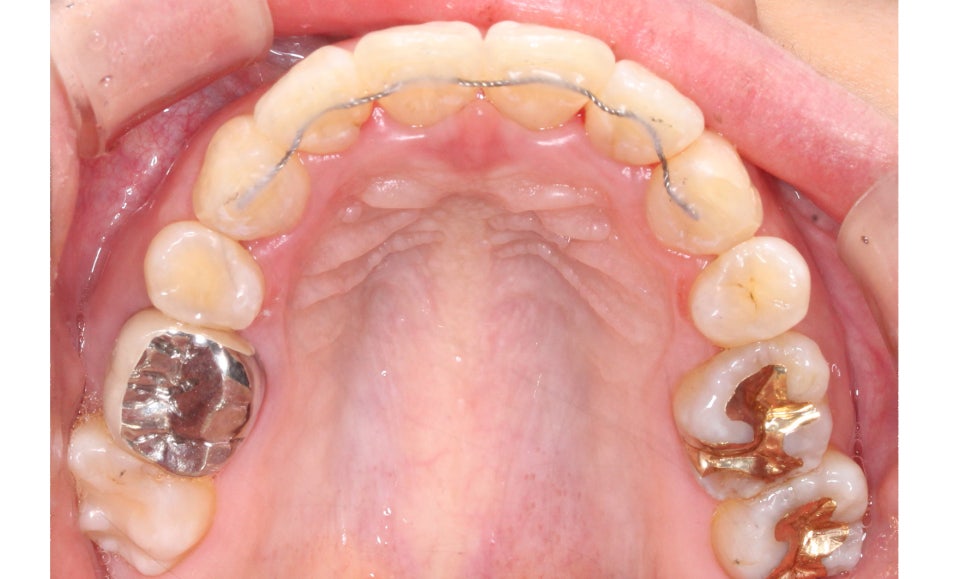

교정 전 상악의 치아배열을 보면

앞니(중절치)부분이 뻐드러져 있고

미세하게 나비치아 성향을 보이는 모습인데요,

마주보듯이 삐뚤어진 상태로

그 모습이 나비의 날개 모습과 비슷하여

이름 붙혀진 증상입니다.